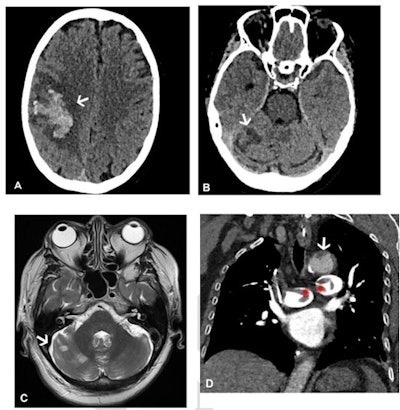

- 73% of the patient cohort presented with neurological symptoms (headache, blurred vision, seizure, collapse) and were confirmed by CT or MR venogram to have a cerebral venous sinus blood clot.

"[Our] findings emphasize that VITT is a multisystem disorder and suggest that whole-body contrast-enhanced imaging is likely to identify further thrombosis," they concluded.